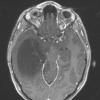

NEOPLASMS (GLIAL)

Astrocytoma, IDH-mutant, WHO Grade 2